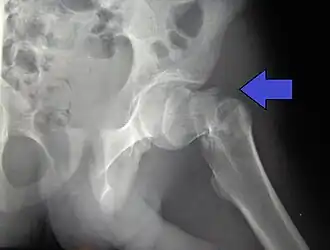

Collumfractuur

De collumfractuur kan volgens de Garden-classificatie worden onderverdeeld in: niet-gedislokeerd (Garden type 1 en 2) en gedislokeerd (Garden type 3 en 4).

De gedislokeerde collumfractuur (Garden type 3 en 4) kan zowel worden behandeld door middel van een osteosynthese of door middel van een endoprothese. Deze keuze is afhankelijk van de leeftijd van de patiënt en de lichamelijke en geestelijke conditie. Wanneer er gekozen wordt voor een osteosynthese zal eerst de heupkop weer recht op het dijbeen gezet moeten worden, dit heet repositie. Als deze stand gelijk is aan de normale stand kan er gebruik worden gemaak van osteosynthesemateriaal. Als repositie niet of onvoldoende lukt wordt er alsnog gekozen voor een endoprothese.[1]

In 20% van de fracturen door de dijbeenhals, groeien de botstukken niet meer aan elkaar. De kans hierop is groter als de botstukken niet operatief worden gefixeerd. Vaak geneest de botbreuk wel, maar is de stand niet optimaal. Door de werking van de spieren worden de botstukken naar elkaar toegetrokken, waarbij ze soms over elkaar heen schuiven en het been korter wordt, in een andere hoek komt te staan of enigszins gedraaid.

Kopnecrose door slechte doorbloeding van de heupkop treedt in 20% van de fracturen van de dijbeenhals op maar is zeldzaam in pertrochantere fracturen. Een gebroken heup kan in zeldzame gevallen bloedvaten en zenuwen beschadigen.